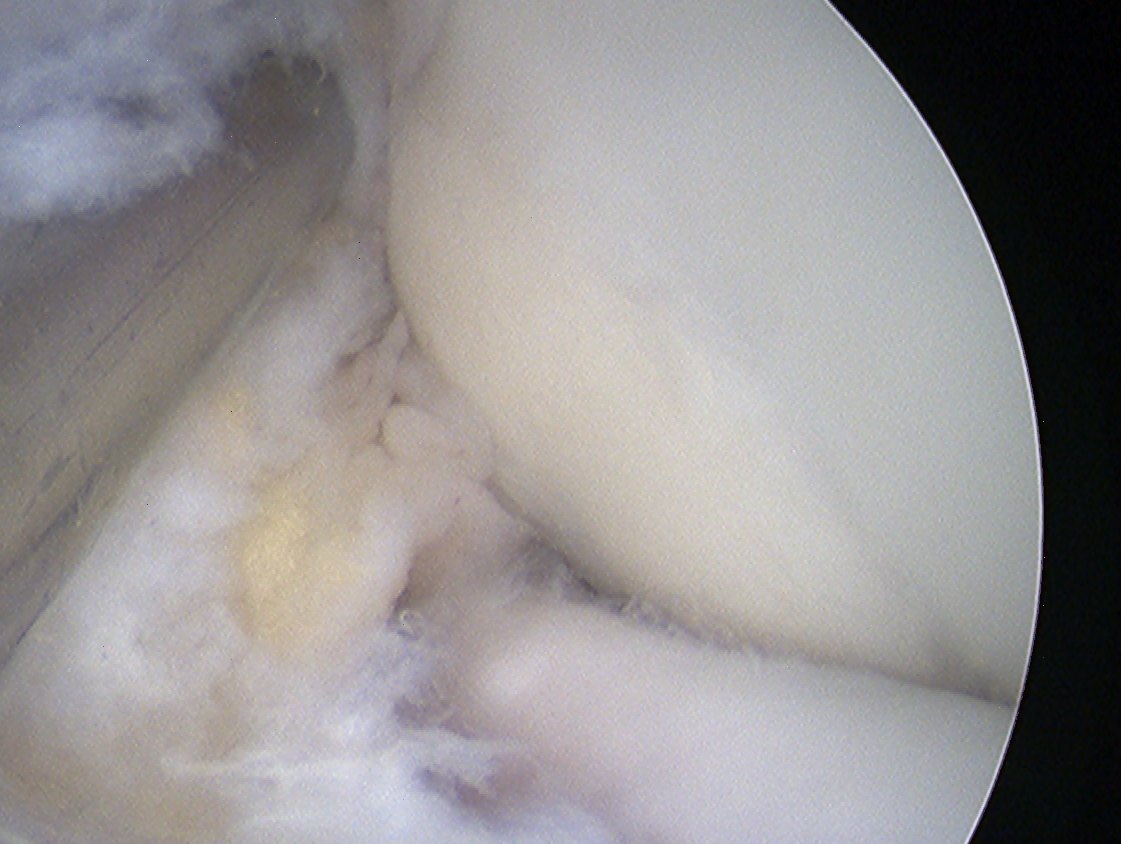

Arthroscopic debridement of loose fragments +/- marrow stimulation

Technique

Elbow arthroscopy

Posterior portals

- capitellar OCD viewed by flexing elbow

Arthroscopic debridement of loose fragments

Arthroscopic debridement of loose fragments and microfracture

Arthroscopic debridement of loose fragments and abrasionplasty